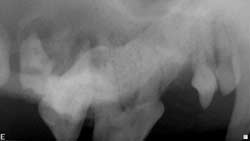

Definitive DiagnosisDental radiographs are obtained to determine or verify which tooth is affected. The affected tooth root will have a periapical lucency around the apex (Figures 3 through 5. View larger image), indicating bone loss.

Multiple views may be required to confirm which tooth is involved, especially when trying to distinguish between an infected maxillary 4th premolar and 1st molar.